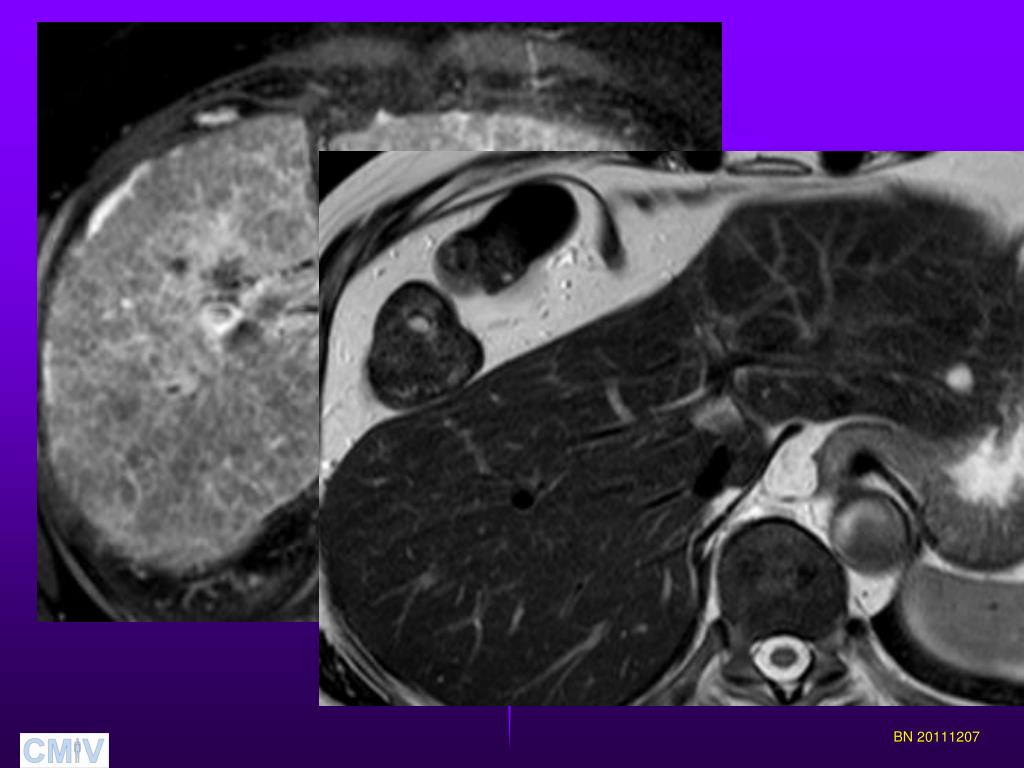

11. Fibrosis/cirrhosis; DCE-MRI Can we identify and separate different stages of fibrosis by quantitatively measure the uptake of Gd-EOB-DTPA (Primovist)using DCE-MRI ? BN 20111207

12. Fibrosis/cirrhosis; DCE-MRI Prospective study. • 38 patients ( 21 men, 17 women) • Pathological liver function tests • Liver biopsy BN 20111207

13. Fibrosis/cirrhosis; DCE-MRI • 1.5 T MR (Achieva, Philips Medical Systems ) • T1-weighted 3D GRE (native, arterial and venous portal phase; 3, 10, 20 and 30 min) KHep – contrast uptake rate LSC_N10 and LSC_N20 LSC10 and LSC20 BN 20111207

14. Fibrosis/cirrhosis; DCE-MRI BN 20111207